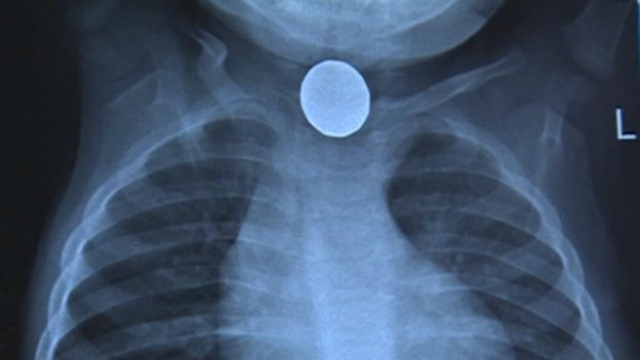

Небольшие батареи, похожие на таблетки или пуговицы, проглотить очень легко. И именно они вызывают ежегодно тысячи травм, многие из которых оканчиваются смертью горе-глотальщика. Такие аккумуляторы можно найти почти везде – от калькуляторов до игрушек. Ознакомившись с проблемой, инженеры из США создали безопасное покрытие для батарей, которое не даст маленьким устройствам причинить организму вред, если они были проглочены.

Изоляция имеет решающее значение в данном вопросе. Травмы и смерти являются следствием высвобождения заряда батареи, которое происходит после проглатывания. Жидкость хорошо проводит ток, молекулы воды разрушаются, производя едкие ионы гидроксида натрия – каустической соды. Это химическое соединение может разъедать ткани, повреждать пищевод или голосовые связки, а иногда достигает крупных кровеносных сосудов. Возникающее внутреннее кровотечение практически невозможно остановить.

На создание покрытия команду во главе с доктором Джеффри Карпом (Jeff Karp) сподвигла статистика: за один лишь 2013 год в США более трёх тысяч травм были спровоцированы проглоченными батареями-таблетками.